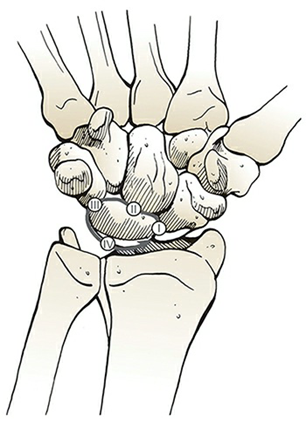

The image shows dorsal dislocation of the capitate which should be congruous with the cup of the lunate.

## Perilunate Dislocations and Fracture-Dislocations The lunate, which is normally securely attached to the distal radius by ligamentous attachments, is commonly referred to as the “carpal keystone.” ## Greater Arc Injury Greater arc injury passes through the scaphoid, capitate, triquetrum, or distal radial styloid and often results in transscaphoid, transcapitate, or transradial styloid perilunate fracture-dislocations.  ## Lesser Arc Injury Lesser arc injury follows a curved path around the lunate, involving only the capsuloligamentous tissues through the scapholunate ligament, midcarpal joint, and lunotriquetral ligaments and results in perilunate and lunate dislocations. The most common injury is transscaphoid perilunate fracture-dislocation. Disruption of the normal kinematics and stability of the carpal row lead to acute failure with a predictable pattern of posttraumatic changes.  ## Mechanism of Injury Perilunate injuries: Axial load is applied to the thenar eminence, forcing the wrist into extension. Injury progresses through several stages (Mayfield progression): It usually begins radially through the body of scaphoid (fracture) or through scapholunate interval (dissociation), although both are possible in the same injury (rare). Force is then transmitted ulnarly through the space of Poirier (between the lunate and capitate). Subsequently, force transmission disrupts the lunotriquetral articulation. This results in dorsal dislocation of the capitate and rest of the carpus relative to the lunate. Finally, the lunate can dislocate volarly out of the lunate fossa of the distal radius, in which case it is called the lunate dislocation. In a lunate dislocation, the proximal part of the capitate sits in the lunate fossa. ## Clinical Evaluation Scapholunate or perilunate injuries typically cause tenderness just distal to Lister tubercle. Swelling is generalized about the wrist with variable dorsal prominence of the entire carpus in cases of dorsal perilunate dislocations. ## Radiographic Evaluation PA, lateral, and oblique views should be obtained to confirm the diagnosis and rule out associated injuries. A CT scan may be useful in further defining the injury pattern. * **PA View** The dislocated lunate appears to be wedge-shaped and more triangular, with an elongated volar lip. Loss of normal carpal colinear “Gilula lines” and abnormal widening of the scapholunate interval >3 mm are noted. Look for associated fractures, such as “transscaphoid” injuries.  * **Lateral View** Most important view. Carefully look at the outline of the capitate and lunate. The “spilled teacup sign” occurs with volar dislocation of the lunate. A clenched-fist PA view obtained after closed reduction of the midcarpal joint is useful for checking residual scapholunate or lunotriquetral dissociation as well as fractures.  ## Classification (Mayfield) | Stage | Description | | :------ | :----------------------------------------------------------------------------------------------------------------------------------------------------------------------------------------------------------------------- | | Stage I | Disruption of the scapholunate joint: The radioscapholunate and interosseous scapholunate ligaments are disrupted. | | Stage II | Disruption of the midcarpal (capitolunate) joint: The radioscaphocapitate ligament is disrupted. | | Stage III | Disruption of the lunotriquetral joint: The distal limb of the radiolunotriquetral ligament and the ulnotriquetrocapitate complex is disrupted. | | Stage IV | Disruption of the radiolunate joint: The dorsal radiolunotriquetral ligament is disrupted, ultimately causing volar dislocation of the lunate. | ## Treatment Closed reduction should be performed with adequate sedation. Closed reduction of lunate dislocations is frequently unsuccessful. Early surgical reconstruction is performed if swelling allows. Immediate surgery including open carpal tunnel release is needed if there are progressive signs of median nerve compromise. Most transscaphoid perilunate dislocations are best treated by open volar and dorsal reduction and repair of the injured structures. Open repair should be supplemented by pin fixation while ligaments heal. Delayed reconstruction is indicated if early intervention is not feasible. ## Complications * Median neuropathy may result from carpal tunnel compression, necessitating surgical release. * Posttraumatic arthritis may result from the initial injury or secondarily from small, retained osseous fragments and cartilage damage. * Chronic perilunate injury may result from untreated or inadequately treated dislocation or fracture-dislocation resulting in chronic pain, instability, and wrist deformity, often associated with tendon rupture or increasing nerve symptoms. * Recurrent instability may necessitate ligament reconstruction with capsular augmentation. * If recurrent instability persists, lunotriquetral fusion may be necessary, with possible concomitant ulnar shortening to tension the volar ulnocarpal ligaments.